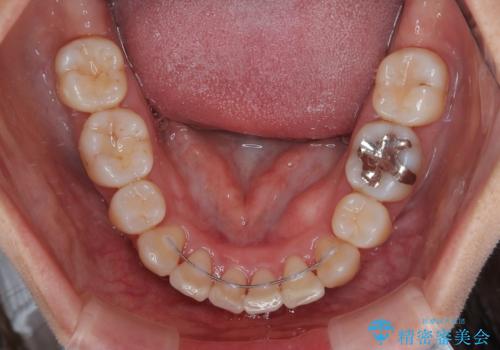

順調に歯が動き、補綴治療も含め2年弱で治療を終えることができました。

横から見た際の口元の飛び出した印象も改善したいとのことで、上下左右の第一小臼歯4本を抜歯し、ワイヤー装置にて抜歯矯正を行うこととしました。

前歯の変色している歯は、神経組織が壊死していたため、矯正治療前に根管治療を実施し、矯正治療後にオールセラミッククラウンにて補綴治療を行うこととしました。